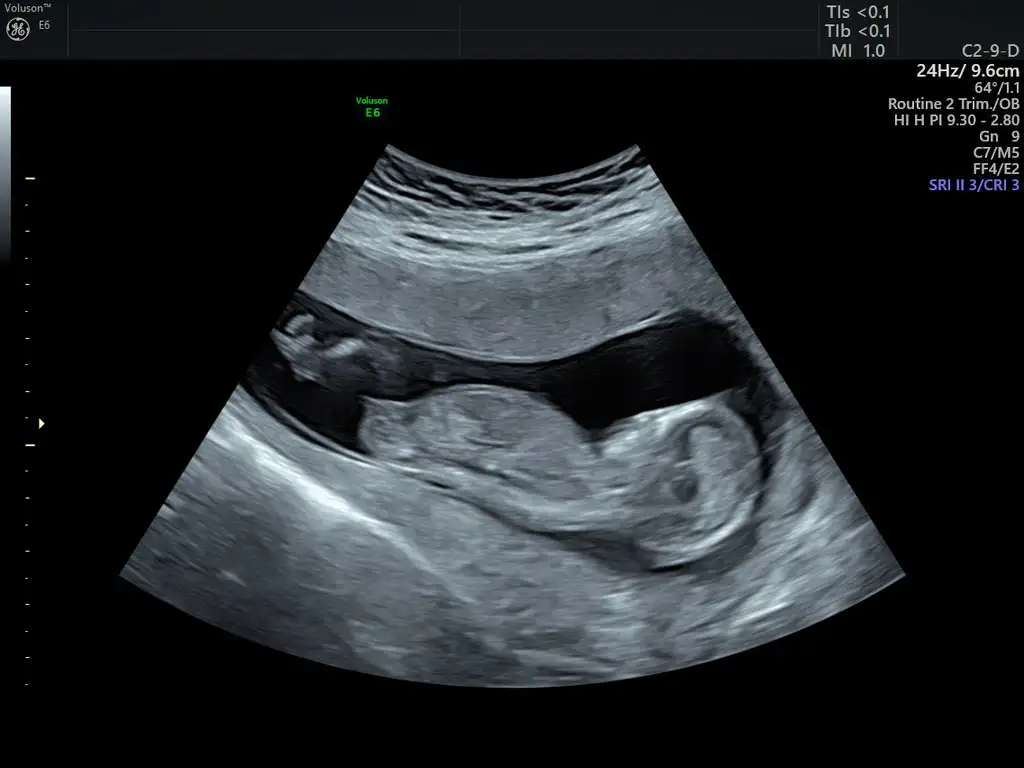

Nubtan hiç anlamıyorum cnm biriler yorumlarsa benzetmeye çalışacağımEki Görüntüle 2248081 kizlar cinsiyet tahmini yaparmisiniz

Hayirli olsun canimEki Görüntüle 2248081 kizlar cinsiyet tahmini yaparmisiniz

Canım kıza benziyorEki Görüntüle 2248081 kizlar cinsiyet tahmini yaparmisiniz